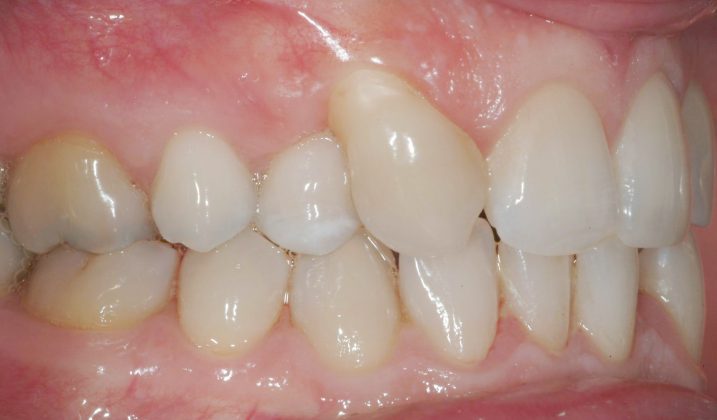

Il protocollo terapeutico ha previsto l’estrazione del primo premolare inferiore sinistro (3.4) e del primo superiore destro (1.4), l’applicazione di una apparecchiatura fissa linguale 2D e di una meccanica asimmetrica di ancoraggio e movimento ortodontico a entrambe le arcate (Figure 3a-b).

Il trattamento è iniziato con l’estrazione dei due premolari in unica seduta in anestesia locale e l’applicazione simultanea, dopo una settimana, della apparecchiatura linguale inferiore e superiore, non essendoci problemi di overbite e potenziali interferenze in occlusione tra l’apparecchiatura superiore e i frontali inferiori. All’arcata superiore è stata effettuata una iniziale chiusura dello spazio estrattivo con forze molto leggere in ancoraggio medio su arco .014” Nichel-Titanio e successivamente .016” Nichel-Titanio, bondato in prima fase per maggior stabilità direttamente sulla superficie mesiale di 2.4.

In seguito, è stato modellato e applicato con tecnica adesiva diretta un pontic estetico in resina composita in sede 1.2, bondato sia distalmente a 1.1 sia mesialmente a 1.3, per un movimento en-masse in ancoraggio medio del gruppo frontale superiore, ottenuto nel settore 1 mediante forza elastica singola su arco .016” acciaio.

Per completare la chiusura degli spazi inferiori in ancoraggio medio è stata applicata una catenella elastica leggera da 3 a 6 ed elastici di Classe II (3/16 da 4.5 once) bilaterali e domiciliari-notturni, applicati vestibolarmente su bottoni estetici bondati su 3.6, 4.6, 1.3 e 2.4 (Figure 7a-e).

La rifinitura del caso ha previsto il completamento del livellamento del piano occlusale posteriore inferiore mediante meccanica cross-over con sezionali in acciaio .017”x .025” applicati sui primi e secondi molari e catenelle di derotazione tra i centrali superiori e tra 1.6 e 1.5 (Figure 8a-b).